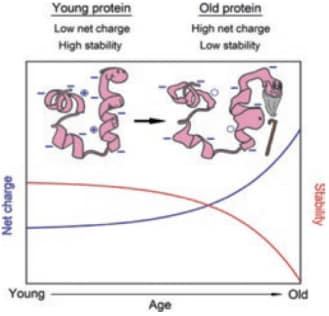

Protein carbonylation is detected and quantified with 2D-oxyDIGE, a novel proteomic approach using specific fluorescent cyanine dyes coupled with hydrazide probes which will react with protein carbonyls.

SOD-1 protein, an antioxidant protein, will be used to measure carbonylation. A panel of different mutations of the SOD-1 protein involved in ALS disease (amyotrophic lateral sclerosis) will be studied and assessed for their susceptibility to carbonylation and to form aggregates.

In order to improve the specificity and the sensitivity of the technique, nanocluster probes are under development to replace theses cy-hydrazide dyes.